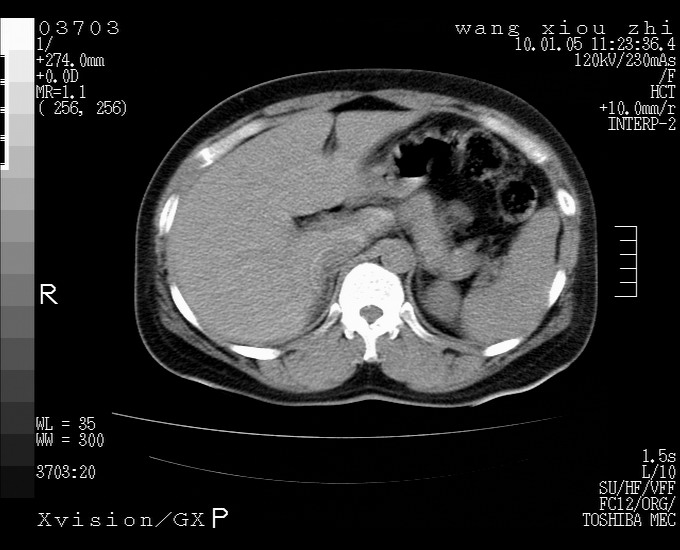

标题: CT23996:f,40.B超提示肿物。

左肾体积增大!下极见一密度略高团状软组织影!肾周结构组织未见明显异常!考虑左肾占位!建议增强!病史?

左肾占位性病变,建议增强。

左肾占位性病变,考虑肾癌,建议增强 。

左肾占位,肾门及腹膜后淋巴结肿大,考虑透明细胞癌可能性大,建议增强

左肾体积增大,内见肿块影,考虑占位,建议增强。